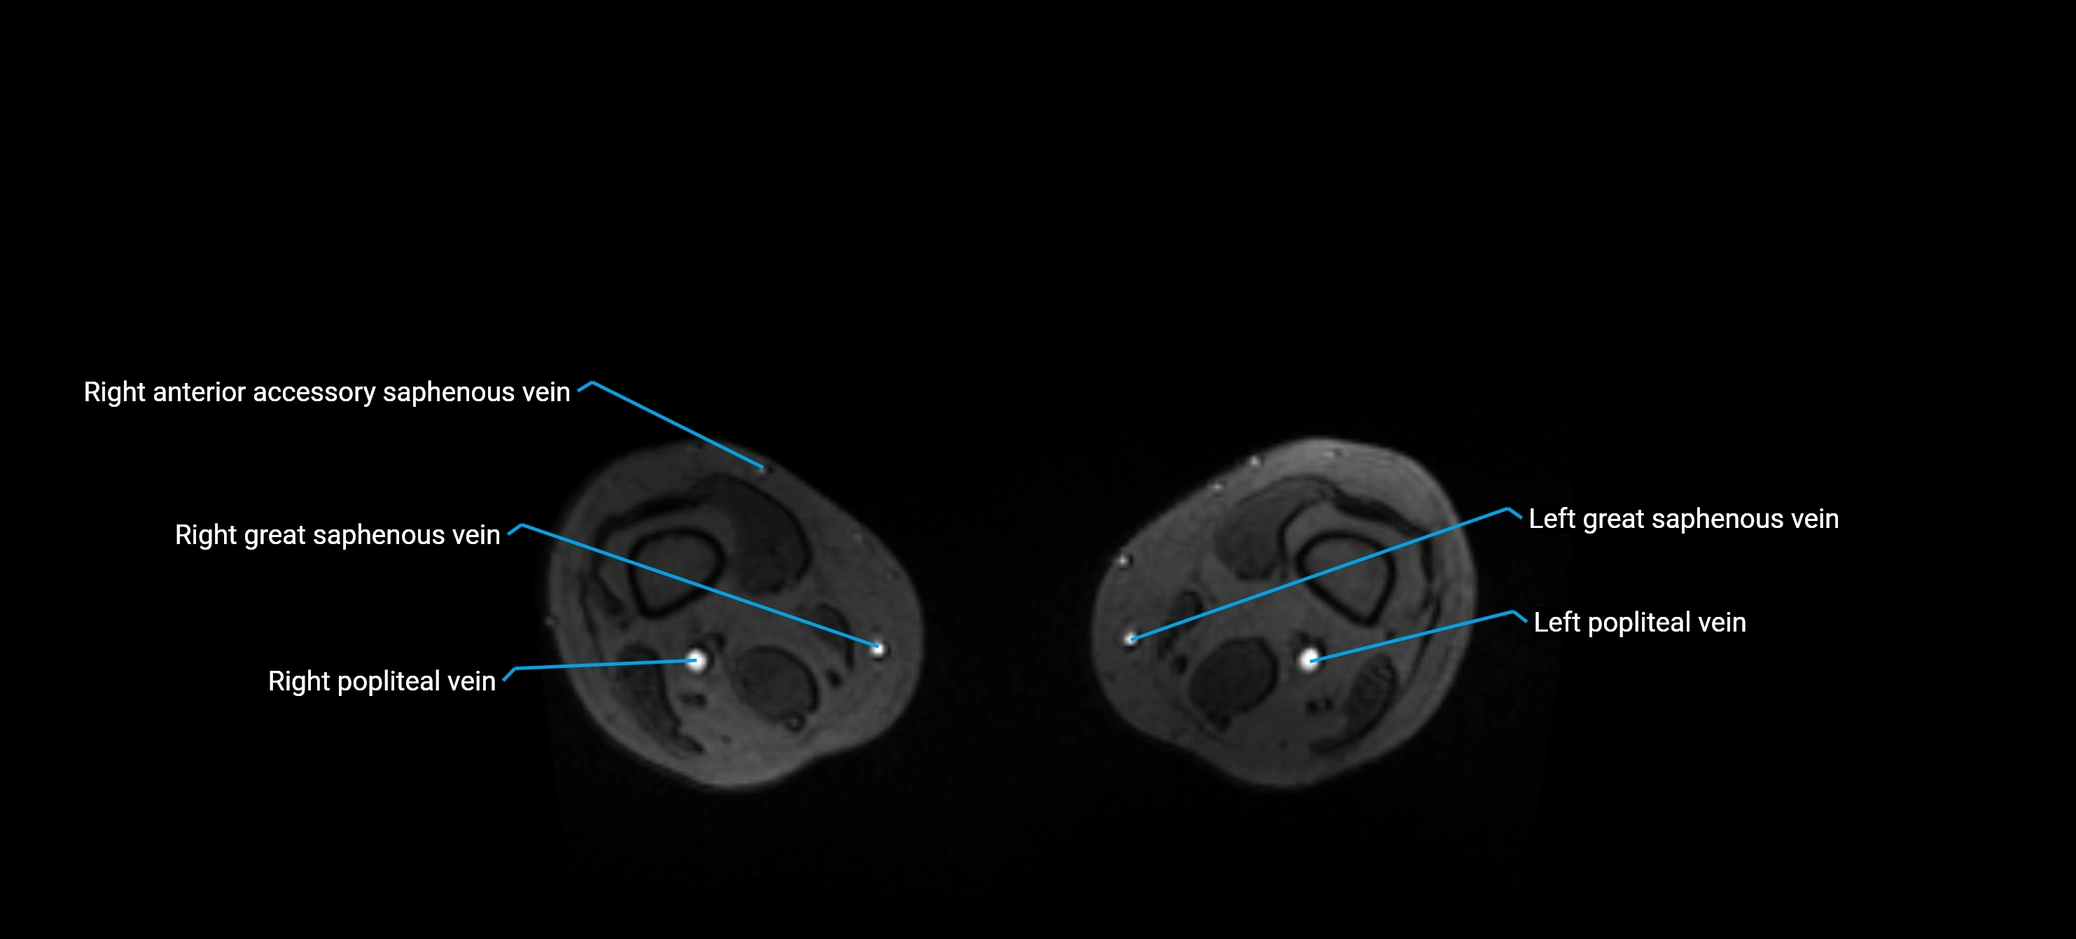

MRI image

image